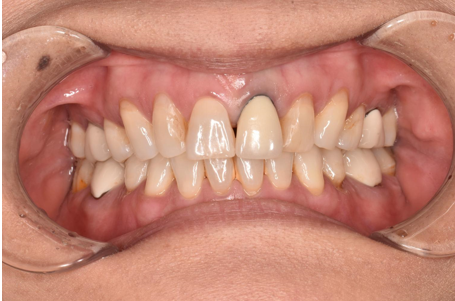

セラミック 2023.0240代女性「銀歯を白くしたい」奥歯の複数の詰め物と被せ物を全てセラミックとジルコニアで白く作り直した症例